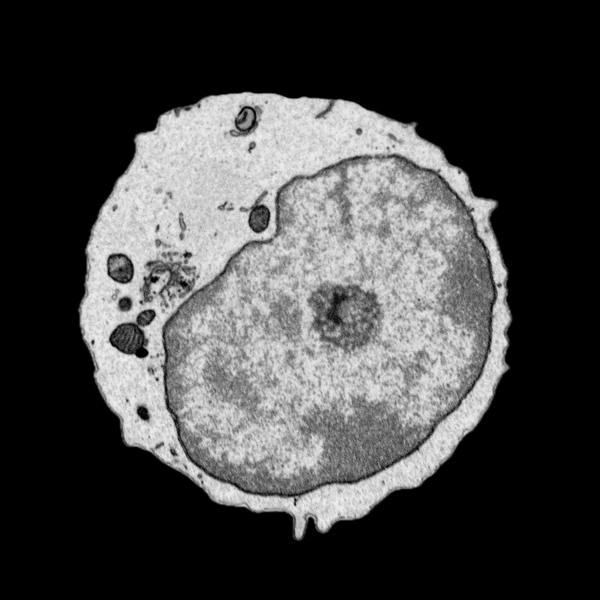

Måndagen den 25 november försvarade Ionut Sebastian Mihai, Institutionen för molekylärbiologi, sin avhandling med titeln "A systems biology single cell approach for querying the differentiation of immune system and antiviral response". Fakultetsopponent var Dr. Karine Chemin från Karolinska Institutet.